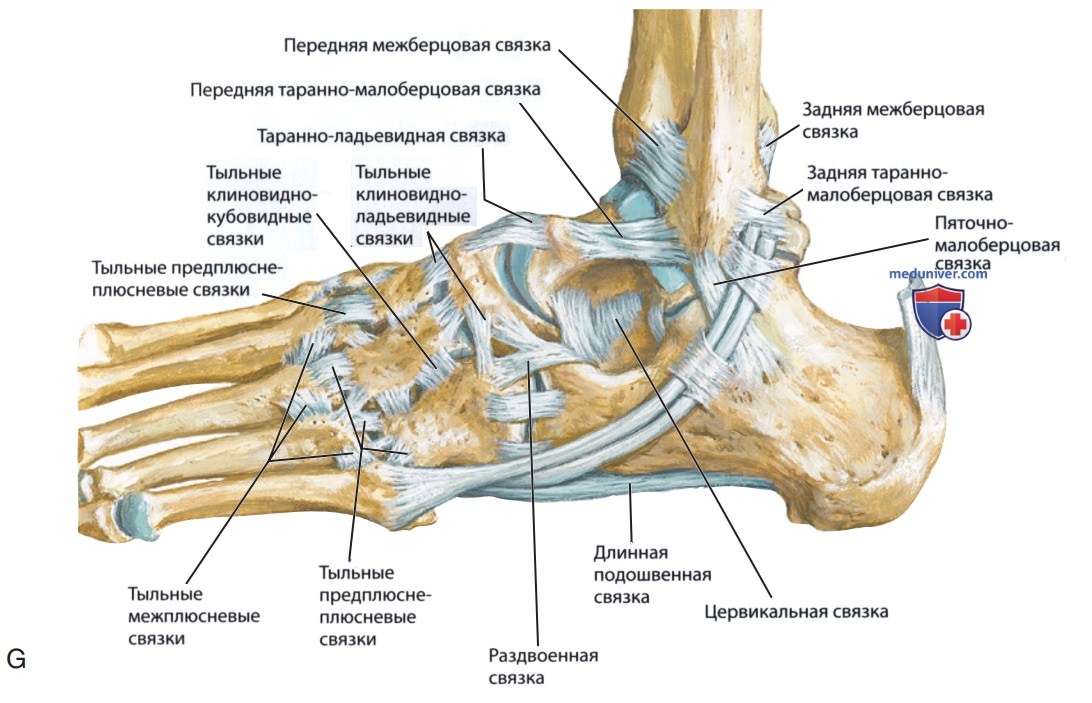

Анатомия голеностопа: Сухожилия и их строение